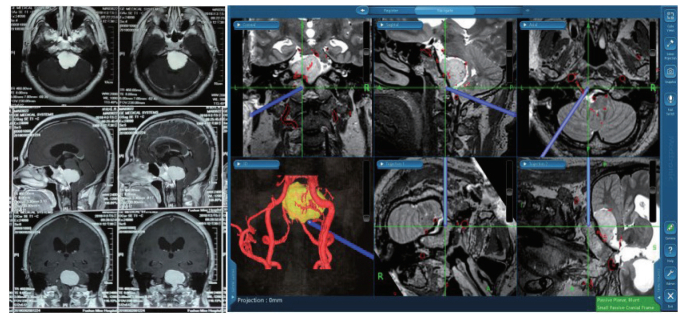

1.4 手术87例患者在全身麻醉下行显微外科手术切除肿瘤,均为颞下经小脑幕入路。多模态组采用多模态神经导航系统辅助切除肿瘤,对照组手术切除肿瘤时则无术中实时影像学指导。多模态组术前将影像数据转移到多模态神经导航系统,通过影像融合和三维重建指导制定手术计划,术中精确定位引导显微手术(图 1)。对照组则根据术者的经验、体表解剖结构、手工测量等方法对肿瘤进行定位,并评估周边结构,其他显微手术操作原则和方法同多模态组。

| 图 1 根据患者术前MRI影像资料进行多模态神经导航系统图像融合及三维重建模型,指示病变及其与周围重要组织结构间的空间关系,术中实时引导显微手术 Fig.1 Image fusion and 3D reconstruction model of multimodal neuronavigation system based on preoperative MRI image data of patients, indicatived lesion and its spatial relationship with the surrounding important tissue structure, real-time guided microsurgery during operation |